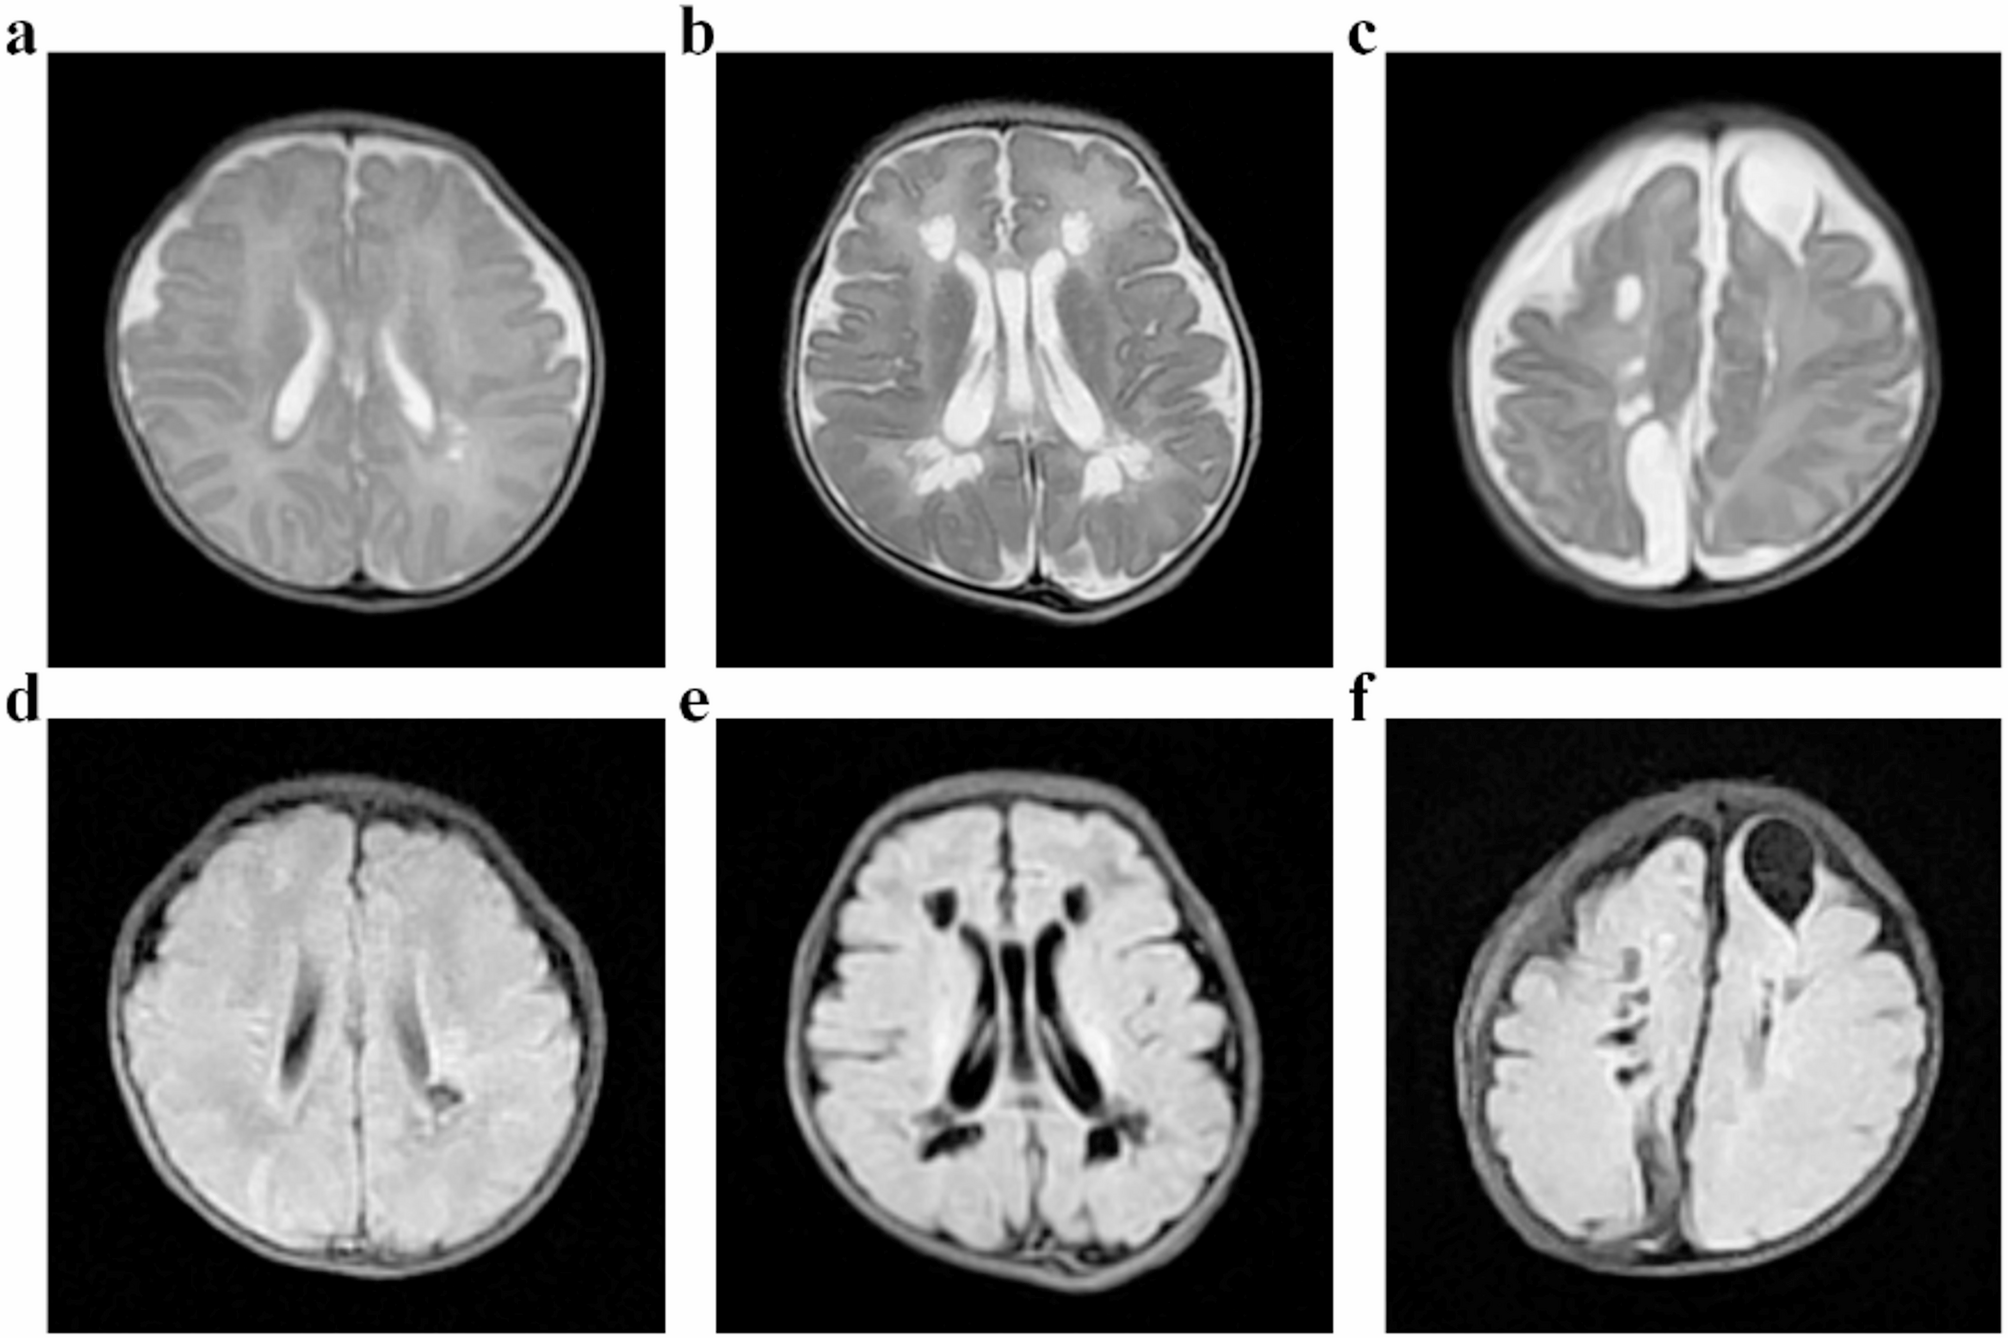

Fig. 1

From: The effect of hemoglobin level in early life on periventricular leukomalacia: a case control study

Three grades of PVL on head MRI. (a). Grade I: local changes in the small capsule cavity around the ventricle (T2WI). (b). Grade II: extensive cystic changes around the ventricle, which could be fused into pieces (T2WI). (c). Grade III: cystic changes in the periventricular and subcortical white matter (T2WI). (d). Grade I: local changes in the small capsule cavity around the ventricle (T2 Flair). (e). Grade II: extensive cystic changes around the ventricle, which could be fused into pieces (T2 Flair). (f). Grade III: cystic changes in the periventricular and subcortical white matter (T2 Flair).